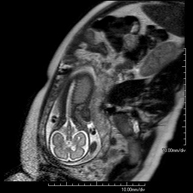

Prova diagnòstica no invasiva que consisteix en l'obtenció d'imatges d'alta definició anatòmica de l'abdomen mitjançant l'ús d'un camp electromagnètic i ones de ràdio (amb un emissor i un receptor). No utilitza radiació ionitzant. En aquesta exploració s'inclouen el fetge, el pàncrees, la melsa, la via biliar, la vesícula biliar, les glàndules suprarenals, els ronyons, l'aorta abdominal, la vena cava inferior, l'estómac, el duodè, etc. En alguns casos caldrà emprar contrast paramagnètic (Gadolini) per caracteritzar les lesions. - RM Pelvis femenina

Prova diagnòstica no invasiva que consisteix en l'obtenció d'imatges d'alta definició anatòmica de la pelvis mitjançant l'ús d'un camp electromagnètic i ones de ràdio (amb un emissor i un receptor). No utilitza radiació ionitzant. Es realitza per a l'estudi de patologies d'úter, d'ovari, de trompes i de vagina, ja siguin d'origen tumoral, inflamatori o vascular. També permet valorar les estructures adjacents localitzades a la pelvis i la identificació de les seves alteracions. De vegades és necessari l'ús de contrast intravenós (Gadolini) per caracteritzar les lesions. - RM Pelvis masculina